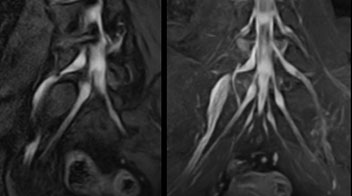

“NerveVIEW can clearly show nerve courses and presence of nerve compression. However, when multiple abnormalities are seen, it can still be hard to determine which nerve is causing the symptoms,” says Dr. Yabuki. “In our experience so far, we see abnormal findings on NerveVIEW in about 70% of elderly patients. As the pain is usually caused by only one nerve, we thus need to find the exact corresponding nerve.”

“With a nerve root block, the patient's pain is improved by infiltration of local anesthesia directly around the nerve root considered to be responsible. Knowing such nerve root block findings prior to image interpretation, helps to easily recognize abnormal findings on NerveVIEW as well. In other words, without a priori knowledge, based on symptoms and/or nerve root block findings, we must be aware of the possibility of overdiagnosis.”

MR neurography attracts referrals at NFMC

The addition of the nerve-selective NerveVIEW sequence to its spine MRI protocol has given NFMC competitive advantages, according to Tanji. “Since we started including NerveVIEW routinely, the demand for lumbar spine MRI examinations has increased, especially for pre-surgical planning purposes and for patients with chronic lower extremity symptoms,” he says.

“Moreover, because no other hospitals in our region are doing nerve plexus imaging yet, we often receive referrals for MR neurography studies from other hospitals even if they have an MRI scanner. Some requests come from as far as 100 km away. NerveVIEW definitely provides us a competitive advantage.”

“Based on our experience, we can certainly recommend NerveVIEW to other centers,” Dr. Yabuki adds. “The sequence opens up many possibilities to facilitate the diagnosis of lower extremity pain and to inform our decision-making regarding therapy and surgery.”